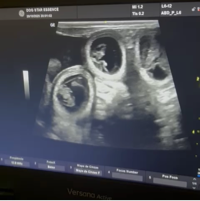

💔 está prenha de 3 filhotes.

• Exames, ultrassons e medicações

• Acompanhamento gestacional